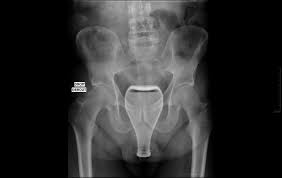

J'ai retrouvé dans un carton un vieux objet qui avait appartenu à un arrière arrière grand oncle prêtre dans la famille. Après quelques recherches sur google image avec les mots : objet religieux, ampoule, gaz, cuivre, tige, magnétisme, etc. je tente ma chance sur ce forum où peut-être quelqu'un pourra donner le nom ou l'utilité de cet objet :